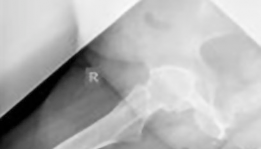

This image depicts a typical hybrid THA construct, showcasing a cemented femoral stem and an uncemented acetabular cup. The distinct fixation mechanisms are visually apparent.